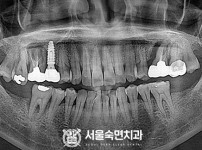

임플란트-전후사진4

치과를-선택할-때-꼭-확인하세요-서울숙면치과-임플란트-전후사진